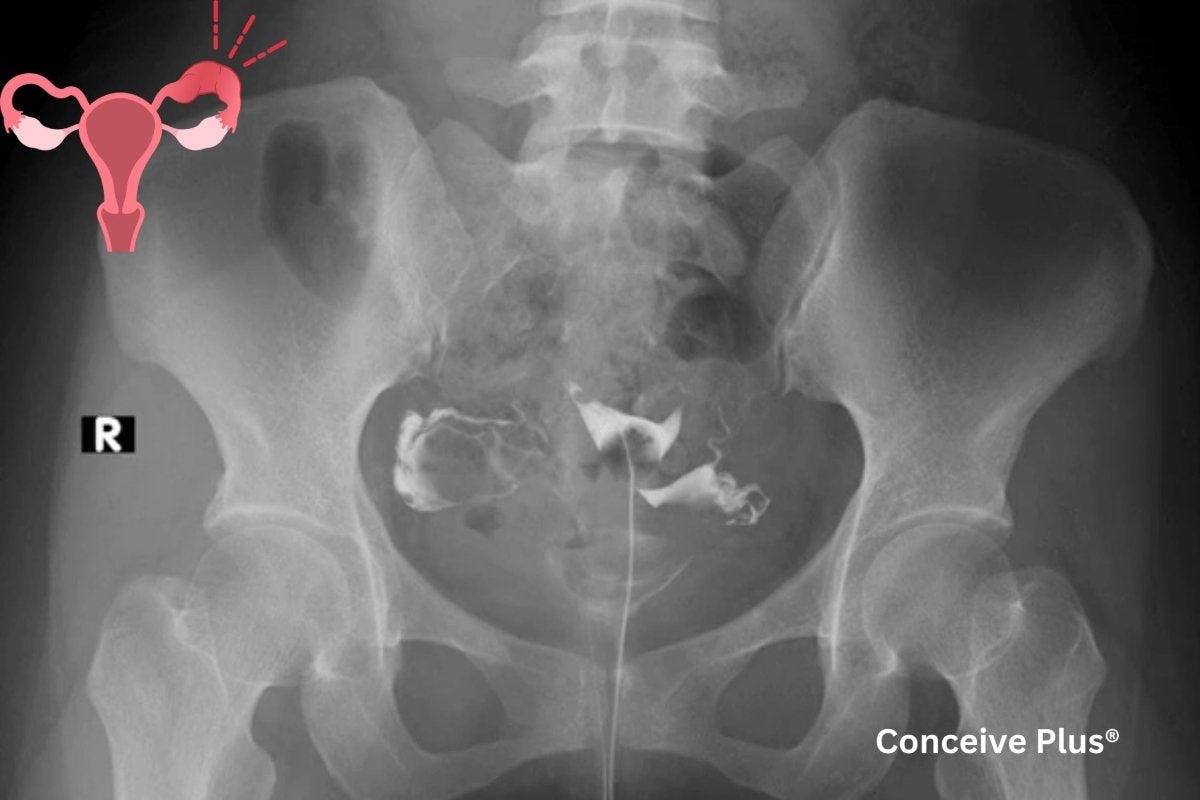

The hysterosalpingogram procedure involves injecting a contrast dye through the cervix, allowing healthcare providers to capture X-ray images of the uterus and fallopian tubes. By evaluating how the dye travels through the reproductive system, specialists can assess whether there are any blockages or structural issues. This test is usually recommended for individuals experiencing difficulty conceiving or when a healthcare professional suspects that the shape or condition of the uterus and fallopian tubes may play a role in fertility challenges.

Because the HSG offers detailed insights, it is often considered one of the initial steps in fertility evaluations. When conducted properly, it can provide pivotal information about uterine fibroids, polyps, scar tissue, or fallopian tube obstruction. Although the procedure itself typically takes only a few minutes, the preparation and follow-up might extend the overall time spent at a healthcare facility [1].